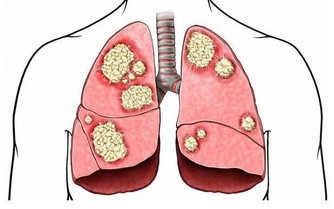

2. 癌症是一種死刑判決

儘管人類在數十年的研究中投入了大量資金,但許多人認為癌症是無法治癒的。但是,雖然癌症可能是一種毀滅性的診斷,但並非沒有希望。免疫療法的新研究,給我們帶來了新的希望,甚至可能完全擊敗它。